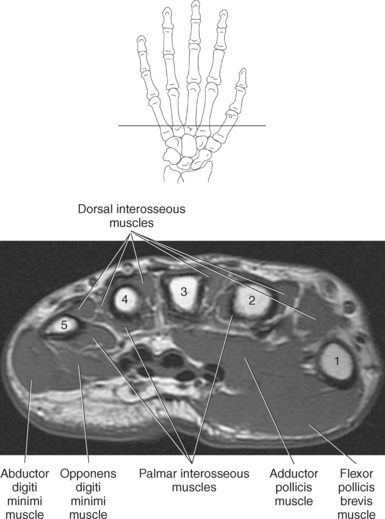

The muscles of the hand can be divided into three groups: (1) metacarpal group (muscles of the metacarpals considered to be the central muscles of the hand), (2) thenar group (muscles involving the thumb and creating the thenar eminence on the radial side), (3) hypothenar group (muscles involving the fifth digit and creating the hypothenar eminence on the ulnar side). These muscles are demonstrated in Figures 9.128 through 9.143.

The metacarpal muscle group includes the interossei and lumbrical muscles. There are seven short interossei muscles in the metacarpal muscle group: three single-headed muscles located on the palmar surface and four double-headed muscles located on the dorsal surface (Figure 9.141, A and B). The four palmar interossei muscles arise from the first, second, fourth, and fifth metacarpals and insert on the corresponding proximal phalanges, frequently radiating into the corresponding tendons of the dorsal aponeurosis. These muscles are responsible for flexion at the MCP joints and extension at the interphalangeal joints. The dorsal interossei arise by two heads from the sides of the five metacarpal bones to insert on the proximal phalanges and radiate onto the dorsal aponeurosis. Like their palmar counterparts, the dorsal interossei flex at the MCP joints and extend at the interphalangeal joints. The four small lumbrical muscles arise from the tendons of the flexor digitorum profundus and pass to the radial side of the corresponding finger to insert on the extensor expansion covering the dorsal surface of the finger (Figure 9.142). The lumbricals flex the first phalanges at the MCP joints and extend the second and third phalanges at the interphalangeal joints.

The four muscles of the thenar group are the abductor pollicis brevis, flexor pollicis brevis, adductor pollicis, and opponens pollicis. The abductor pollicis brevis is a thin, flat superficial muscle arising from the transverse carpal ligament, navicular, and trapezium (Figure 9.143). It runs inferiorly and laterally to insert on the base of the first phalanx of the thumb to abduct the thumb. The flexor pollicis brevis has two heads: The superficial or lateral head arises from the flexor retinaculum, and the deep or medial head arises from the trapezium, trapezoid, and capitate. This muscle inserts on the radial and ulnar base of the first phalanx to flex, adduct, and abduct the thumb (Figure 9.143). Frequently, a sesamoid bone can be found in the insertion tendon on the radial side. The adductor pollicis also has two heads: The transverse head arises from the dorsal aspect of the third metacarpal, and the oblique head arises from numerous slips off the capitate, bases of the second and third metacarpals, and the sheath of the flexor carpi radialis tendon. The adductor pollicis inserts onto the base of the first phalanx of the thumb to provide adduction and assist in the opposition and flexion of the thumb (Figures 9.142 and 9.143). The opponens pollicis provides the main opposition for the thumb but also assists with adduction. It arises from the trapezium and flexor retinaculum and inserts onto the radial aspect of the first metacarpal (Figures 9.142 and 9.143). These muscles are also demonstrated in sequential Figures 9.128 through 9.140.

The hypothenar group consists of three muscles: abductor digiti minimi, flexor digiti minimi brevis, and opponens digiti minimi. The abductor digiti minimi muscle arises from the pisiform and the flexor retinaculum to end in a flat tendon that inserts onto the ulnar base of the first phalanx of the little finger (Figures 9.142 and 9.143). The abductor digiti minimi muscle is the main abductor of the little finger. The flexor digiti minimi brevis muscle arises from the flexor retinaculum and the hook of the hamate. It fuses with the tendon of the abductor digiti minimi to insert on the base of the first phalanx of the fifth digit (Figures 9.142 and 9.143). The flexor digiti minimi brevis flexes at the MCP joint. Like the flexor digiti minimi brevis muscle, the opponens digiti minimi arises from the hook of the hamate and the flexor retinaculum (Figure 9.143). It inserts on the ulnar surface of the fifth metacarpal to bring the little finger into the position for opposition. For the hand muscles, see Figures 9.128 through 9.140.